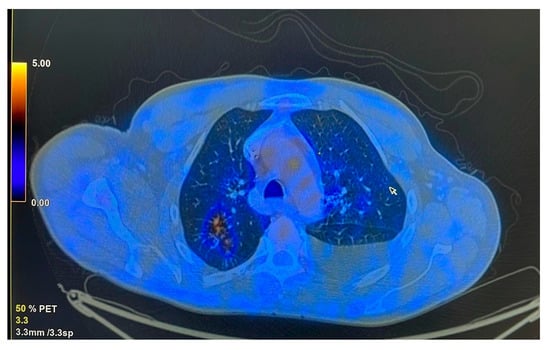

The patient was referred to the pulmonology department following combined imaging exploration (computed tomography—CT; positron emission tomography—PET) which revealed multiple pulmonary micro- and macronodular lesions with diffuse contours, located in the segments of both upper lobes and the right Fowler segment, with varying degrees of metabolic activity (Figure 1). Additionally, a flat, moderately enhancing lesion was located on the left lateral pleura, along with left pleurisy. There were also flat, metabolically active lesions at the level of the inner surface of the diaphragmatic domes and large-volume ascites.

Figure 1. Metabolic activity in the posterior segment of the right upper lobe (RUL).